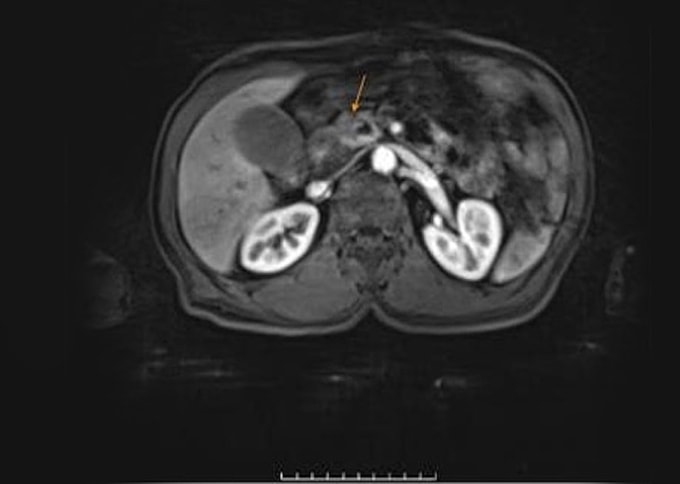

Sau vài tuần uống thuốc khi chỉ số men gan tăng cao, da và củng mạc mắt chuyển sang màu vàng, ông Quang đến Bệnh viện Đa khoa Tâm Anh TP HCM khám. Kết quả xét nghiệm cho thấy men gan của ông Quang cao hơn 30 lần so với bình thường, trong đó ALT (GPT) lên tới 1.600 U/L (bình thường khoảng 50 U/L). Chụp CT tụy và MRI ổ bụng ghi nhận tổn thương tại vùng đầu tụy kích thước khoảng 20 mm, chèn ép và xâm lấn túi tụy, giãn ống tụy 7 mm, thành túi mật phù nề, ống mật chủ giãn trong và ngoài gan.

Tổn thương bất thường ở vùng đầu tụy trên ảnh CT. Ảnh Bệnh viện Đa khoa Tâm Anh

BS.CKII Võ Ngọc Bích, Khoa Gan - Mật - Tụy, Trung tâm Nội soi và Phẫu thuật Nội soi Tiêu hóa, chẩn đoán ông Quang bị ung thư tụy, diễn tiến rất nhanh. Khối u nằm ở đầu tụy, cần thực hiện kỹ thuật cắt khối tá tụy (Whipple) nhằm loại bỏ toàn bộ khối u, ngăn xâm lấn và di căn sang các cơ quan khác.